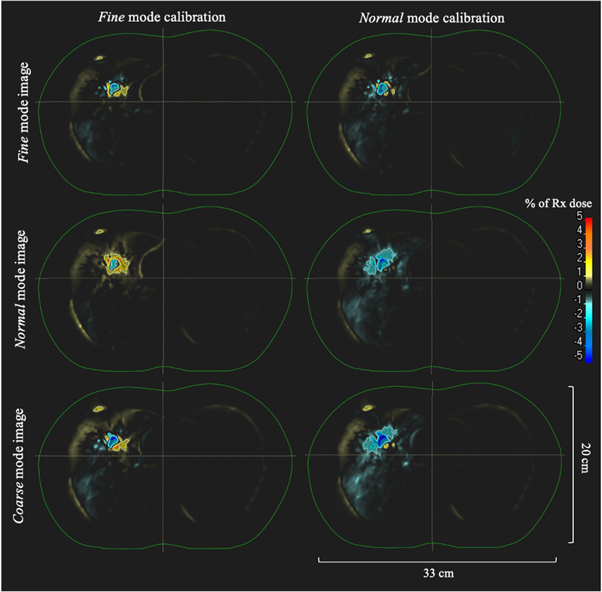

An axial image displaying isodose lines overlaid on the CTV and PTV contours for the dose calculation with the planning CT thorax phantom image set for the large volume treatment plan is shown in figure 3. Figure 4 shows dose-difference maps for axial image slices (corresponding to that seen in figure 3 for the planning CT) for each ClearRT acquisition and calibration mode evaluated in the study. Tables 2 and 3 show relative and absolute differences in selected target volume and OAR DVH metrics used to assess plan quality for ClearRT in comparison to the planning CT. The most clinically relevant DVH parameters compared for the target volumes (CTV and PTV) were the dose to 98% of the volume (D98, near-minimum dose), D95 (related to the prescription dose), Dmean, and D2 (near-maximum dose), while the most relevant parameters compared for the critical structures (OARs) were Dmean and D2. Additionally, figure 5 shows relative differences for all DVH metrics evaluated (including those listed in table 2 as well as D99, D50, and D1) for the target volumes for each of the ClearRT acquisition modes and calibrations assessed in this study.

Standard image High-resolution imageFigure 4. Dose-difference maps for each ClearRT acquisition and calibration mode for the large volume treatment plan. The external contour is displayed in green. Differences are shown as the percent difference relative to the prescription dose over the entire treatment course between the ClearRT image set and the planning CT image set (ClearRT minus planning CT). The axial image slices displayed correspond to that of the planning CT shown in figure 3.

Figure 5. Dose relative to the planning CT for all target volume DVH metrics evaluated (n = 7) for the large volume treatment plan for ClearRT images of the thorax phantom with each calibration mode applied.

Standard image High-resolution imageThe differences in calculated target volume DVH parameters for the ClearRT system relative to the planning CT were all within ±1.5% regardless of the mode used for the thorax phantom acquisition or the mode used to acquire the calibration curve, while nearly 40% of DVH parameters were within ±0.5% (18 of 48). The median difference between target volume dose parameters was smallest for the Fine mode thorax phantom acquisition with the Fine mode calibration (med: −0.1%, min: −0.3%, max: +0.2%) and the Coarse mode thorax phantom acquisition with the Normal mode calibration (med: −0.1%, min: −0.6, max: +0.2). Note that the dose difference for Coarse mode being lower with the Normal mode calibration as compared to the Fine mode calibration is likely a result of Coarse mode image acquisition parameters being more similar to Normal mode. Overall, application of the Fine mode calibration resulted in slightly 'hot' (higher dose) target volume dose distributions relative to the planning CT, while application of the Normal mode calibration resulted in slightly 'cold' (lower dose) dose distributions as observed in figures 4 and 5. DVH parameters for the OARs were generally 'hot' relative the planning CT with the exception of the dose to the skin. For the skin, differences of over 20 cGy over the entire treatment course were observed for the D2 parameter as shown in table 3. However, doses were well within those specified in the clinical goals utilized during the plan optimization process, and thus these values would not be a concern clinically for this particular treatment plan.